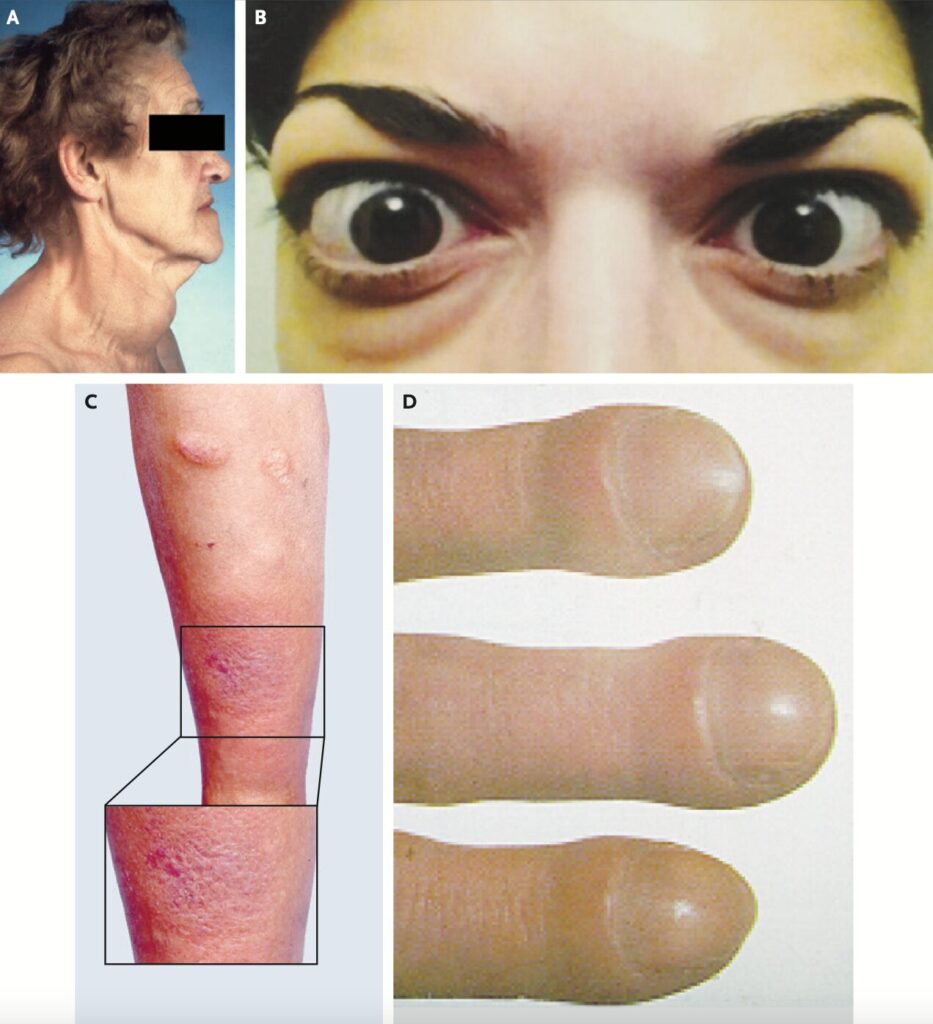

身体所見